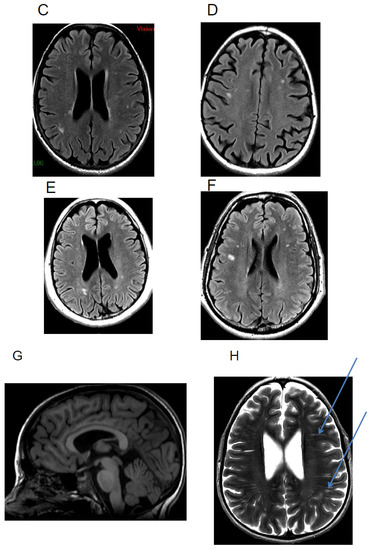

5.3. White Matter Hyperintensities

5.4. Others